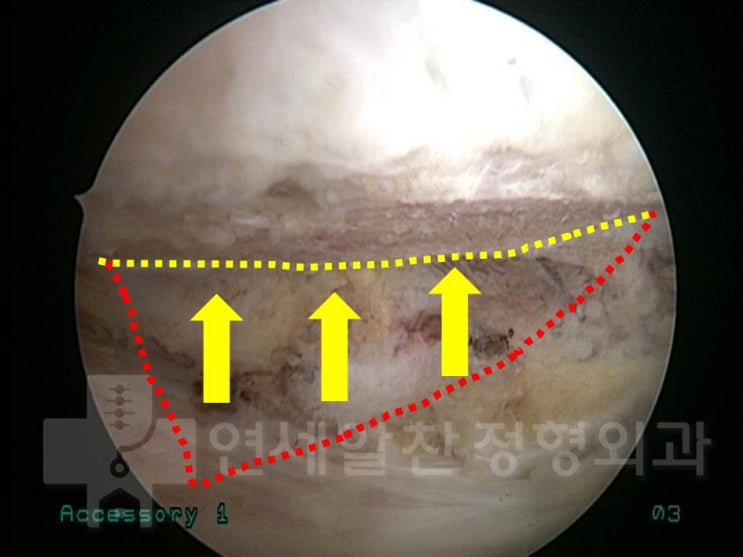

안녕하세요. 정형외과 전문의 이동규 입니다. 오늘은 회전근개 파열에서 관절경 수술시 더 단단하게 봉합하...

2021. 11. 25.